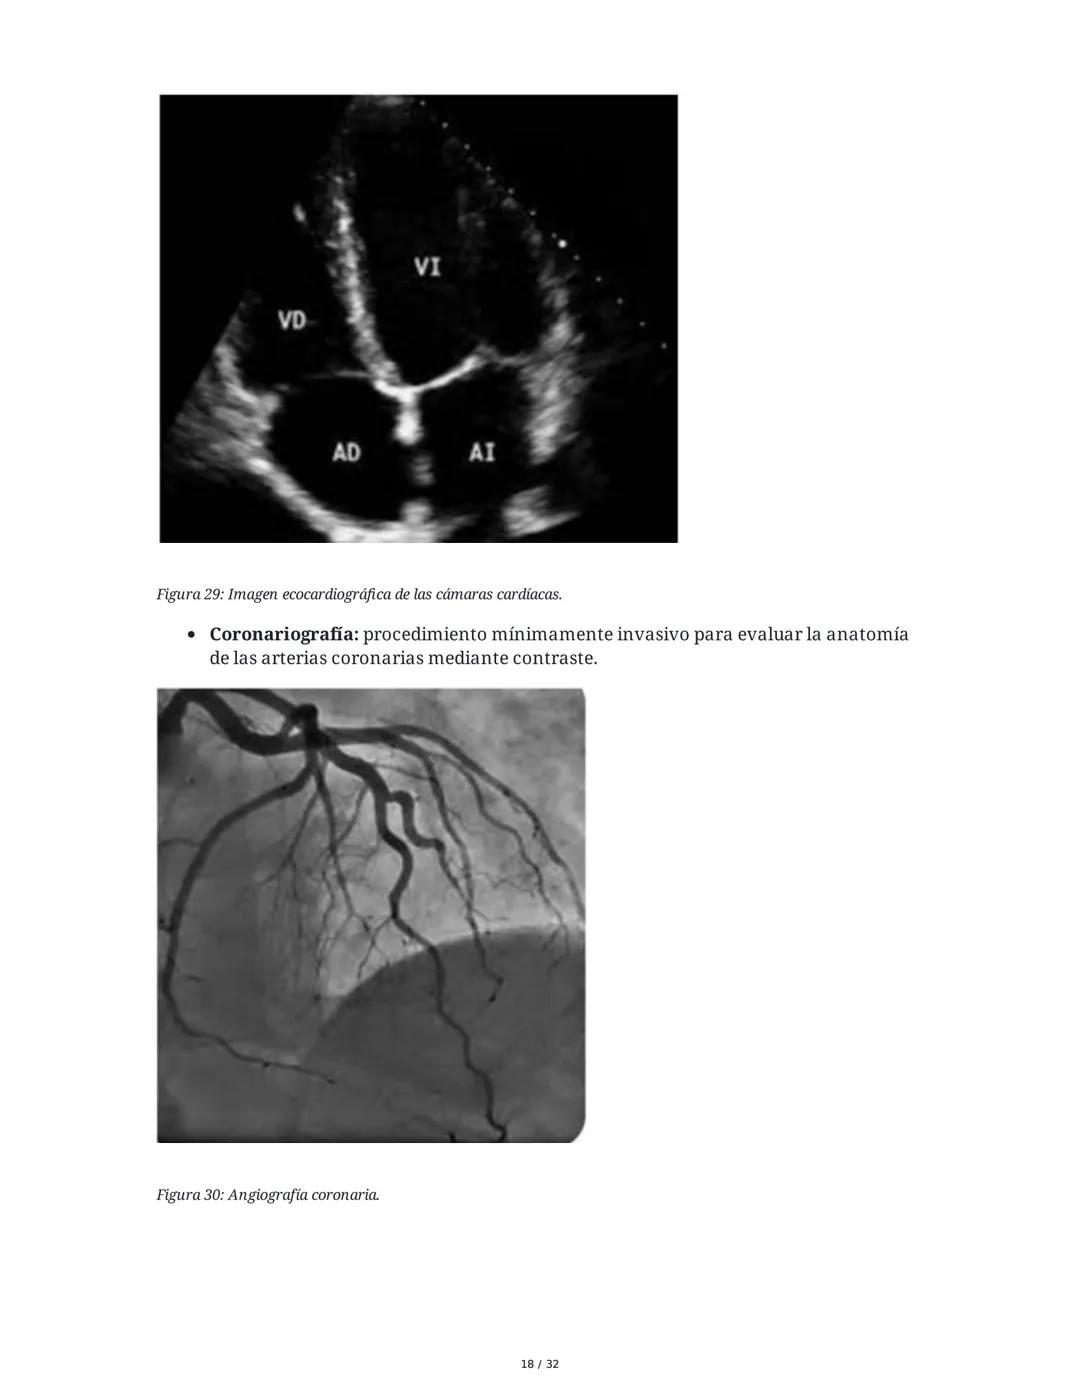

Estudios complementarios: La ecocardiografía evalúa la función cardíaca, mientras que la coronariografía permite visualizar directamente las arterias coronarias mediante contraste.